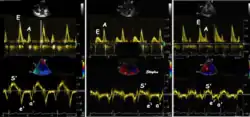

As the ventricle relaxes, the annulus moves towards the base of the heart, signifying the volume expansion of the ventricle. The peak mitral annular velocity during early filling, e' is a measure of left ventricular diastolic function, and has been shown to be relatively independent of left ventricular filling pressure.[12][13][14] If there is impaired relaxation (Diastolic dysfunction), the e' velocity decreases. After the early relaxation, the ventricular myocardium is passive, the late velocity peak a' is a function of atrial contraction. The ratio between e' and a' is also a measure of diastolic function, in addition to the absolute values.

During the two filling phases, there is early (E) and late (A) blood flow from the atrium to the ventricle, corresponding to the annular velocity phases. The flow, is driven by the pressure difference between atrium and ventricle, this pressure difference is both a function of the pressure drop during early relaxation and the initial atrial pressure. In light diastolic dysfunction, the peak early mitral flow velocity E is reduced in proportion to the e', but if relaxation is so reduced that it causes increase in atrial pressure, E will increase again, while e', being less load dependent, remains low. Thus, the ratio E/e' is related to the atrial pressure, and can show increased filling pressure[15][16] although with several reservations.[17][18] In the right ventricle this is not an important principle, as the right atrial pressure is the same as central venous pressure which can easily be assessed from venous congestion.[19][20]